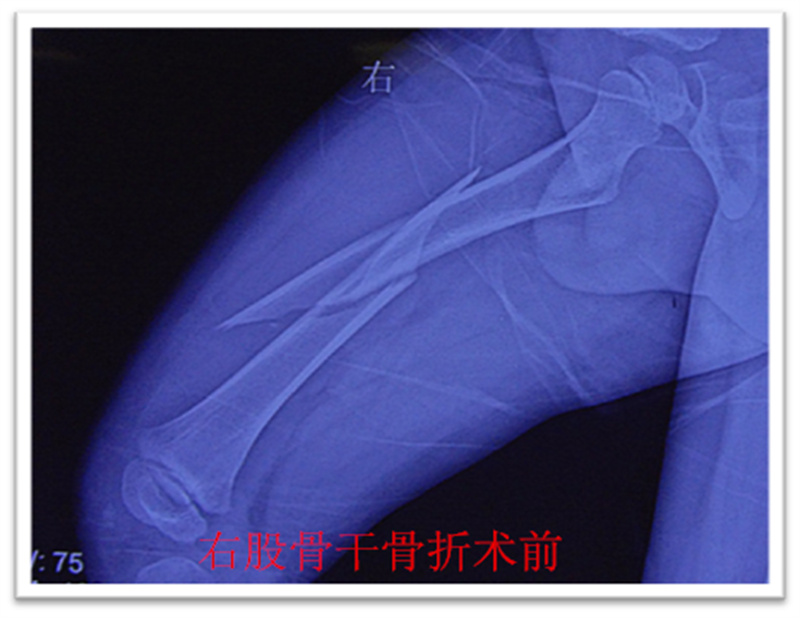

,弹性髓内钉内固定解决了这个矛盾。有人说,弹性髓内钉的出现是上天对儿童的恩惠。的确,弹性髓内钉是治疗小儿长管状骨骨骨折的一种理想、可靠的内固定方法。弹性髓内钉技术发源于法国,在欧洲广泛应用后,现已为全球所接受,被称为是儿童骨科界的一次革命。徐州儿童医院骨一科应用弹性髓内钉技术治疗四肢长管状骨骨折,具有创伤小、恢复快、并发症相对少,孩子能较快恢复正常生活、学习等优点。该技术先将骨折闭合复位,通过微小的切口将特制的弹性髓内钉置入骨髓腔,达到固定骨折的目的。适用于肱骨,股骨,尺桡骨等部位的常见骨折(图)。